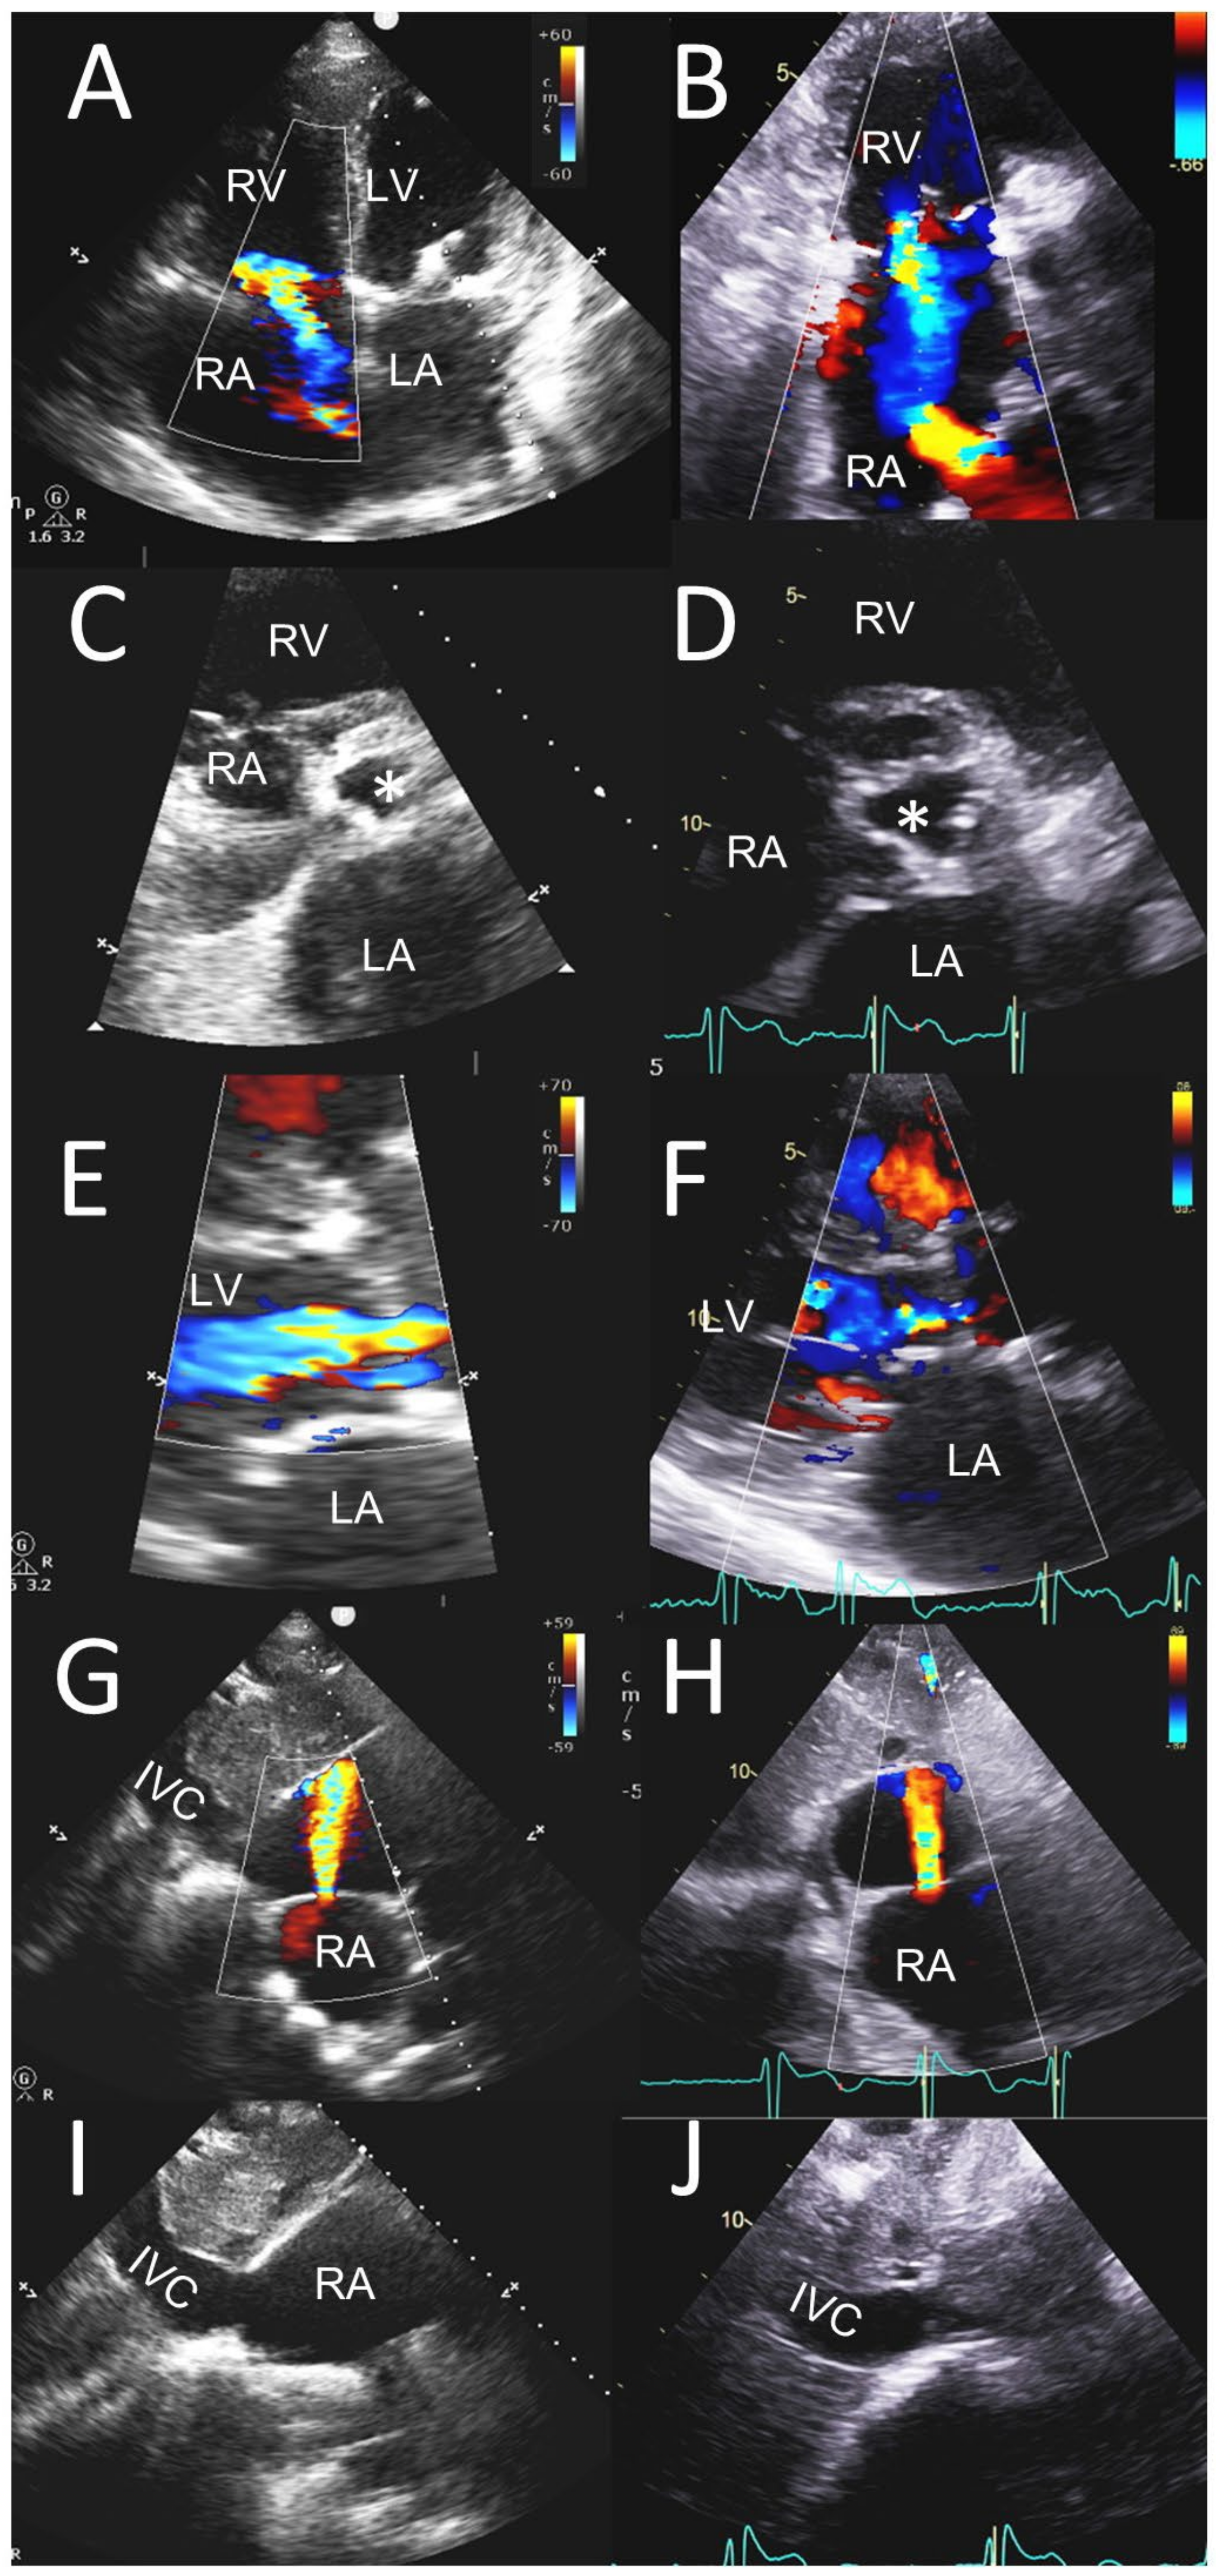

3.2. ≥Moderate Valvular Regurgitation

| Mitral regurgitation | 16 (20.8) | 17 (22.1) |

| Aortic regurgitation | 10 (13.0) | 11 (14.3) |

| Aortic stenosis | 15 (19.5) | 18 (23.4) |

| Tricuspid regurgitation | 13 (16.9) | 14 (18.2) |

| Paravalvular leak on MV | 2 (2.6) | 2 (2.6) |

| Paravalvular leak on AV | 2 (2.6) | 2 (2.6) |

| Aortic prosthetic valve stenosis | 1 (1.3) | 1 (1.3) |